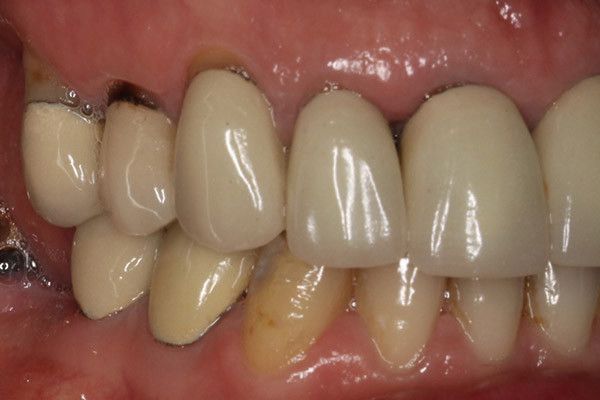

Bọc răng sứ bị đen nướu là một trong những vấn đề phổ biến sau khi thực hiện thẩm mỹ răng. Nguyên nhân của tình trạng này thường xuất phát từ chất lượng kém của răng sứ kim loại. Răng sứ kim loại bao gồm phần sứ bên trong được đúc từ kim loại và phần bên ngoài được phủ nhiều lớp sứ để tự nhiên hóa. Sau một thời gian sử dụng, tác động của môi trường nước bọt trong miệng có thể gây ra hiện tượng oxy hóa làm cho phần kim loại bên trong bị đen và lộ ra ngoài.

Cách chăm sóc răng không đúng cũng là một nguyên nhân chính có thể dẫn đến tình trạng bọc sứ bị đen nướu. Khi chải răng không đúng kỹ thuật, nướu gần chân răng có thể bị tuột lên, làm mài mòn phần sứ ở chân răng và dần dần lộ ra phần kim loại phía bên trong. Do đó, nếu không chú ý đến cách chăm sóc răng đúng cách, có thể tạo điều kiện cho tình trạng nướu thâm và đen.

Kỹ thuật bọc răng sứ bị đen

Kỹ thuật bọc sứ đóng vai trò quan trọng trong việc xác định liệu răng sứ có bị đen hay không. Nếu kỹ thuật này không chính xác, có thể làm cho phần nướu ở chân răng lộ ra gây ảnh hưởng đến thẩm mỹ. Nếu có khoảng trống giữa răng sứ và nướu, thức ăn sau khi nhai có thể bám vào chân răng gây tác động đến chất men và làm thâm nướu.